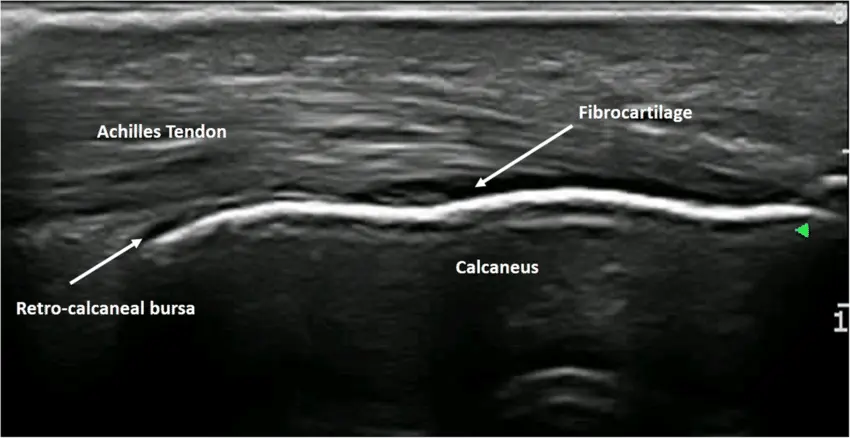

Tanıyı doğrulamak ve eşlik edebilecek diğer yaralanmaları dışlamak amacıyla düz radyografi, ultrasonografi veya manyetik rezonans görüntüleme (MRI) gibi görüntüleme yöntemleri kullanılabilir. Travma öyküsü olan hastalarda kırık ihtimalini dışlamak için öncelikle radyografi önerilir.

Ultrason ve MRI, Aşil tendon kopması şüphesini doğrulayabilmekle birlikte, klinik tanı kriterlerinin MRI’dan daha yüksek duyarlılığa sahip olduğu belirtilmektedir. Bununla birlikte MRI, yüksek maliyet, zaman kaybı ve cerrahi planlamayı geciktirebilme potansiyeli nedeniyle rutin olarak kullanılmamalıdır. Bu nedenle MRI’ın yalnızca bulguların belirsiz olduğu, subakut veya kronik olgularda ve cerrahi öncesi değerlendirme amacıyla tercih edilmesi önerilmektedir10.